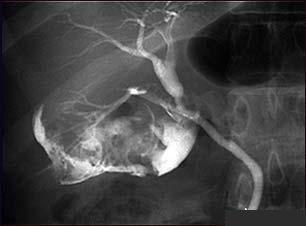

Colecistita